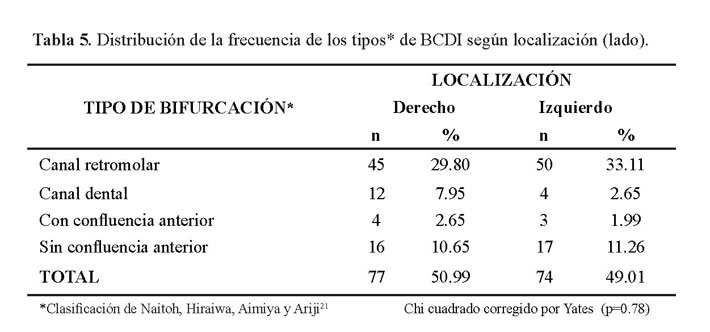

En la tabla 5 se muestra que no hubo diferencia estadísticamente significativa entre ambos lados (p=0.78) (Figura 5 y figura 6).

En la tabla 3 se describe la distribución de la frecuencia del tipo de BCDI donde se encontraron 103 casos del tipo canal retromolar (Figura 2, figura 3 y figura 4); no se encontró ningún caso con el tipo de bifurcación canal bucal-lingual.

Del total de casos encontrados con BCDI el 93.79% (151 casos) fueron unilaterales y 6.21% (10 casos) bilaterales (Tabla 4).